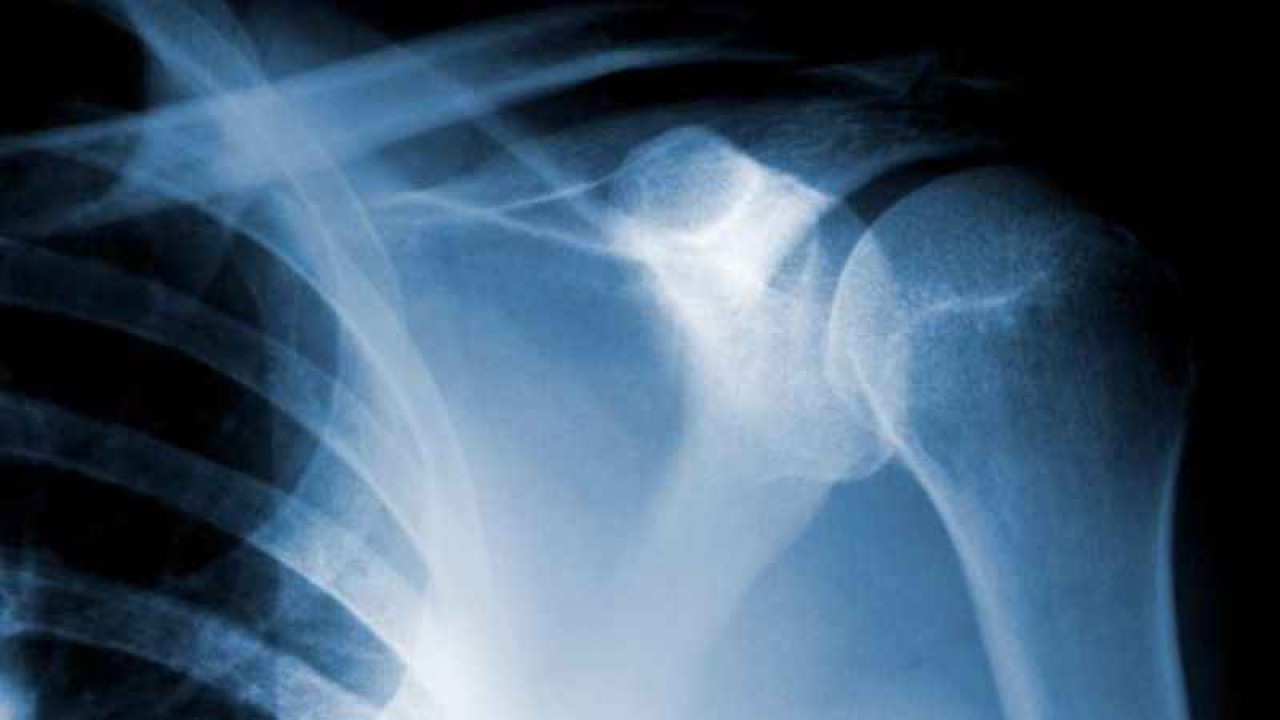

Kireçlenme, tıbbi adıyla osteoartrit, eklemlerde meydana gelen bir aşınma ve yıpranma durumudur. Bu durum genellikle kıkırdak dokunun zayıflaması ve sonunda aşınması ile karakterizedir. Kıkırdak, eklemlerinizi kaplayan ve kemikler arasındaki sürtünmeyi azaltan yumuşak ve kaygan bir dokudur. Kireçlenme gelişimine neden olan faktörler çok çeşitlidir ve bunlar genetik yatkınlık, yaşlanma, eklemi etkileyen kronik stres veya yaralanmalar ve obeziteyi içerebilir.